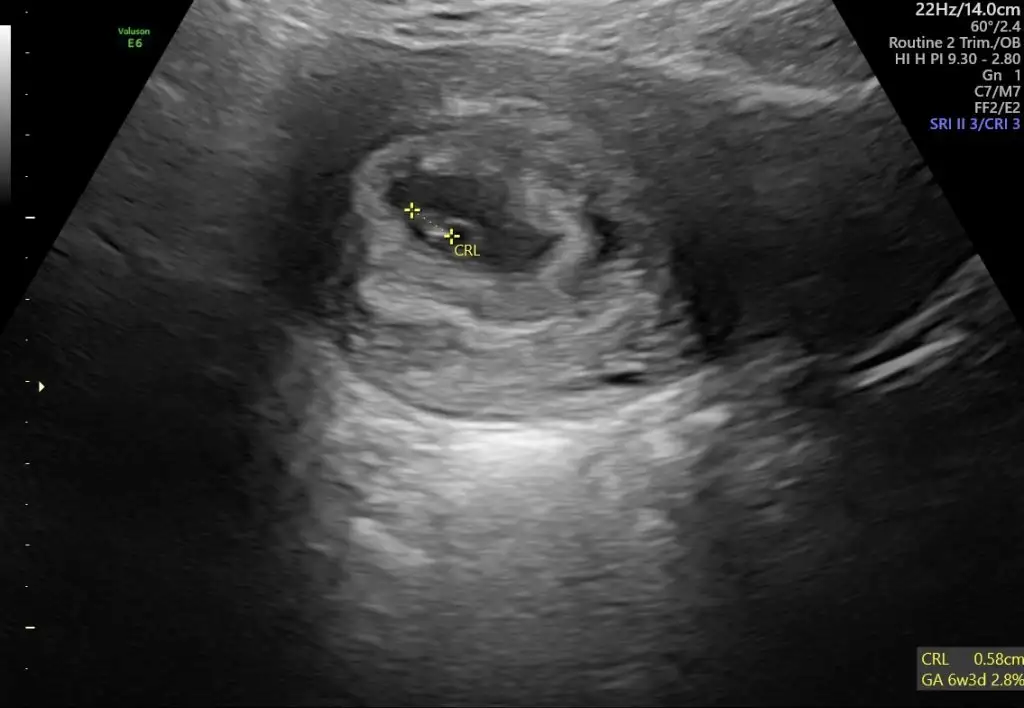

5., 6., ve 9+5 .haftaya ait karından ultrason görüntüleri :)Eki Görüntüle 3273013 Eki Görüntüle 3273014 Eki Görüntüle 3273015